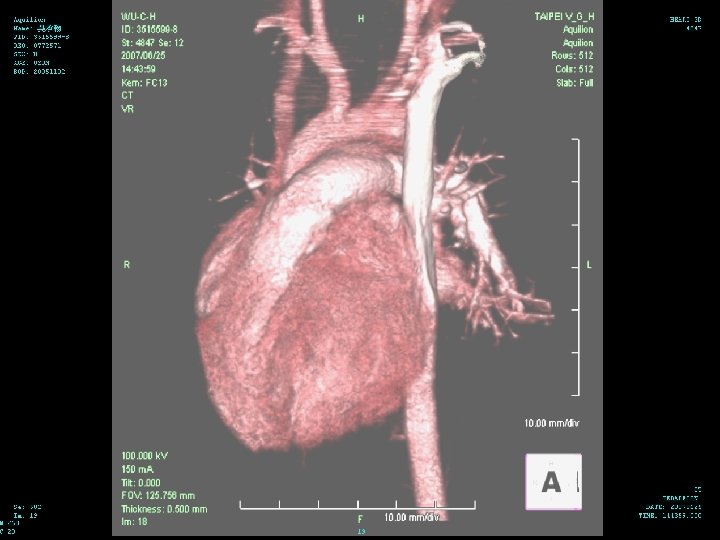

Hospital Course (6/25 -28) 3 D CT of chest performed on 6/25 n There is narrowing of the trachea in the level of aortic arch with narrowest diameter about 0. 25 cm about 1. 2 cm in length n There is dextrocardia with left side aortic arch n There is double SVC with left SVC drainage to coronary sinus n

Diagnosis identification of a right aortic arch on chest radiograph n An ill-defined arch location is often observed in patients with double aortic arch n compression of the trachea and hyperinflation and/or atelectasis of some of the lobes of either lung n chest radiography is not very sensitive n

Diagnosis CT/MRI/Angio:These expensive radiological studies are rarely necessary to evaluate vascular rings n Although these modalities provide excellent delineation of all of the associated structures, they should be reserved for cases in which the results of barium esophagram do not provide a clear diagnosis n